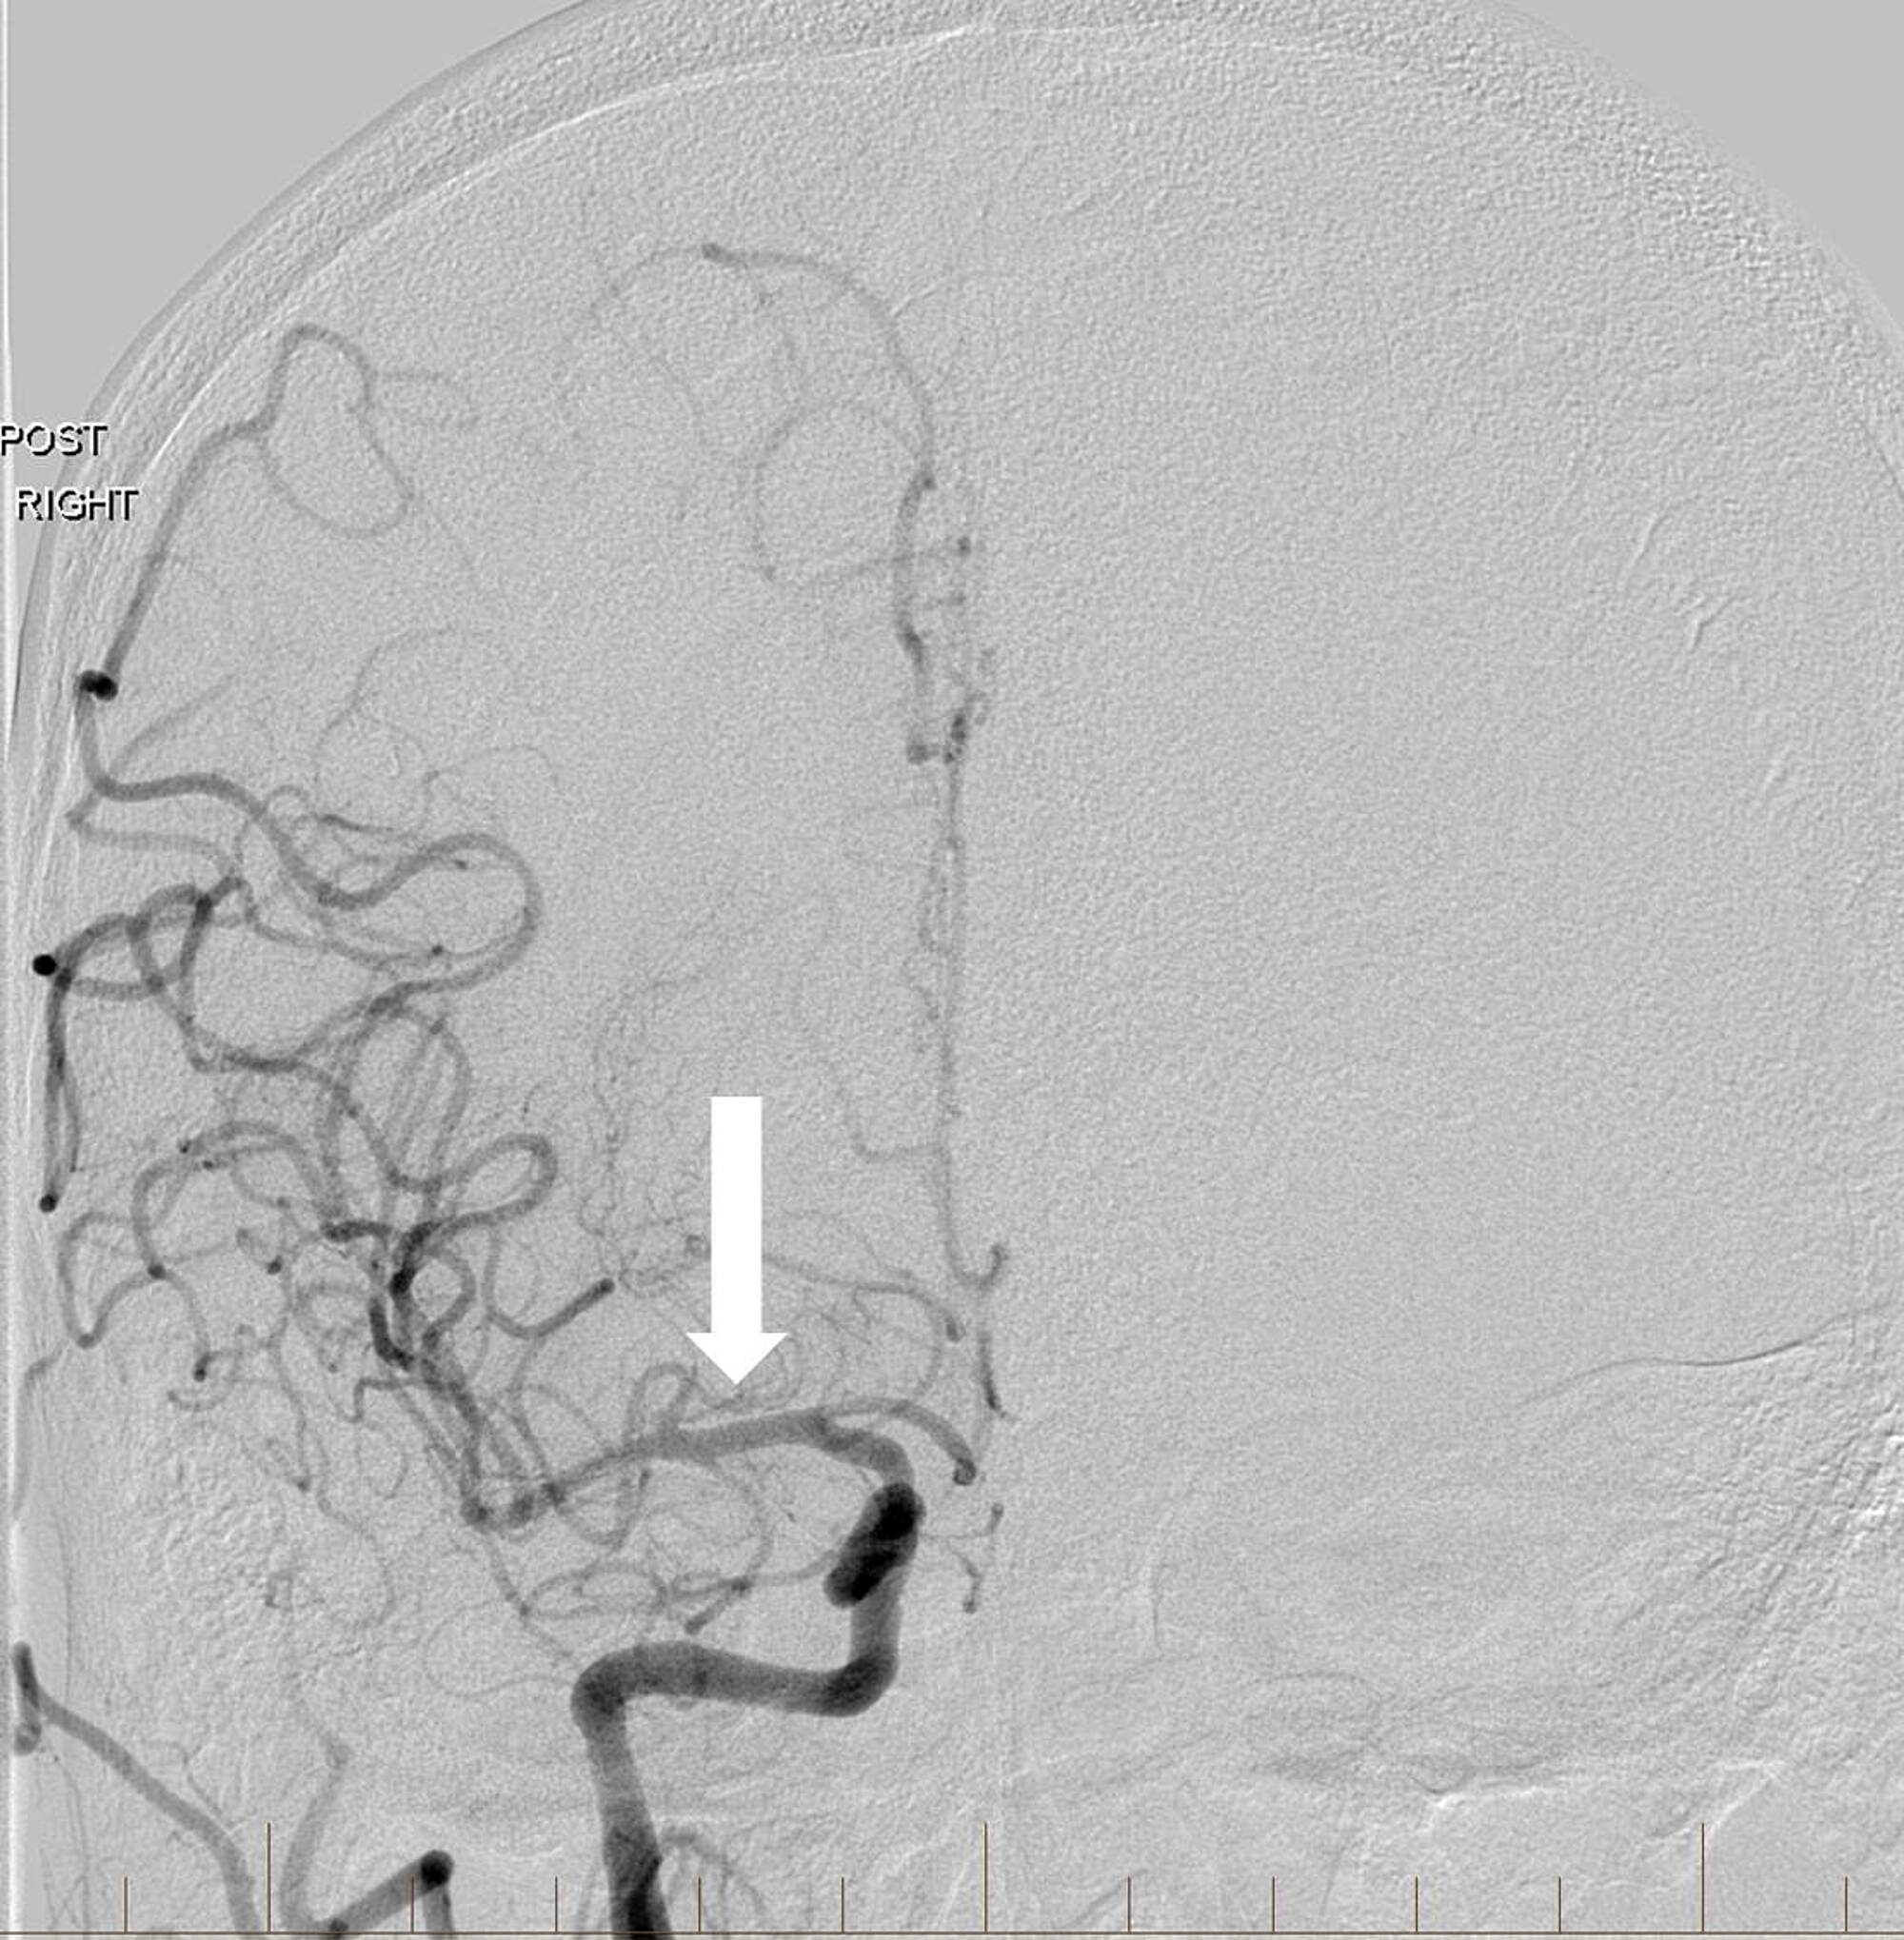

A 63-year-old man with a history of hypertension, hyperlipidemia, peripheral artery disease, smoking, and Stage IV lung cancer presented with left-sided weakness and dysarthria when he visited our institution for a chemotherapy port placement. His National Institutes of Health Stroke Scale (NIHSS) score was six and he was not a candidate for intravenous (IV) thrombolytics. Computed tomography angiography (CTA) revealed occlusion of the extracranial right internal carotid artery (ICA) and right middle cerebral artery (MCA) but no hemorrhage or large areas of acute ischemic change. Biplane digital subtraction angiography (DSA) revealed tapering to occlusion of the proximal right cervical ICA at the level of the carotid artery bulb (Figure 1).

Angioplasty was performed at the level of the severe proximal ICA occlusion using a 4 mm x 20 mm noncompliant balloon. Subsequent angiography demonstrated the progression of contrast into the distal cervical and intracranial segments of the ICA with a persistent severe and irregular stenosis. A decision was then made to stent using distal embolic protection. A 4-mm diameter distal protection device was advanced and deployed in standard fashion within the distal cervical ICA at the level of C1-C2. An eptifibatide infusion was started, and an 8 mm to 6 mm tapered self-expanding carotid stent measuring 40 mm in length was positioned across the lesion and deployed in the standard fashion without angiographic complications. Post-stenting angiography revealed a 90% improvement in the caliber of the occluded vessel without delay in transit time throughout all cervical and intracranial right ICA segments (Figure 2).